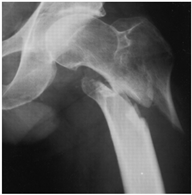

For X-ray 4, four scenarios were developed.![]() | Scenario 1: What would be your operation preference for a mobile patient aged 50–70 and with an ASA score of 1–2? Scenario 2: What would be your operation preference for a mobile patient aged 71 years or older with an ASA score of 1–2? Scenario 3: What would be your operation preference for a mobile patient aged 50–70 with an ASA score of 3–4? Scenario 4: What would be your operation preference for a mobile patient aged 71 years or older with an ASA score of 3–4? |